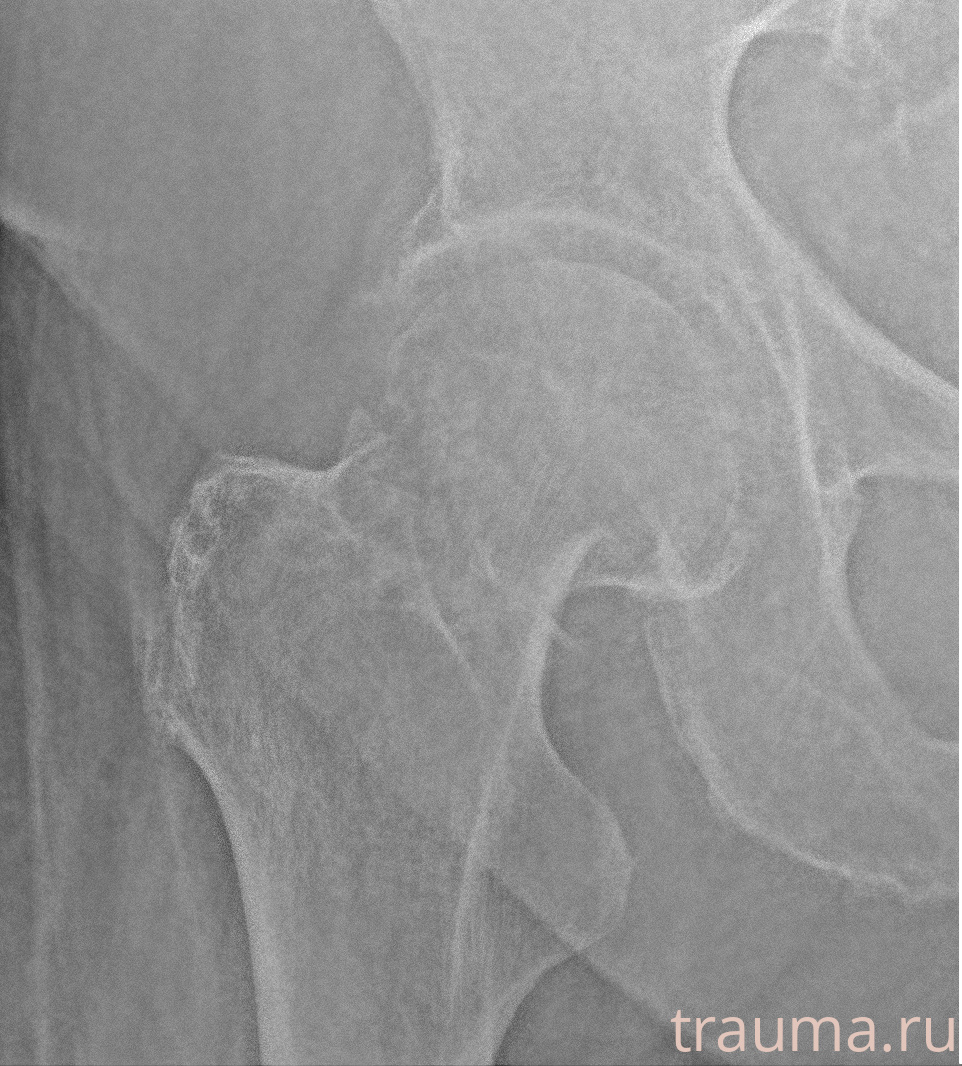

Рентгенограммы

Рентген на дому: по вашему адресу приезжает врач-рентгенолог, травматолог-ортопед с мобильным рентгеновским аппаратом, проводит диагностику травмы или заболевания, делает необходимые рентгенограммы, дает рекомендации по дальнейшему лечению. Получить качественные снимки в домашних условиях возможно благодаря уникальной методике, разработанной МосРентген Центром для института  Склифосовского